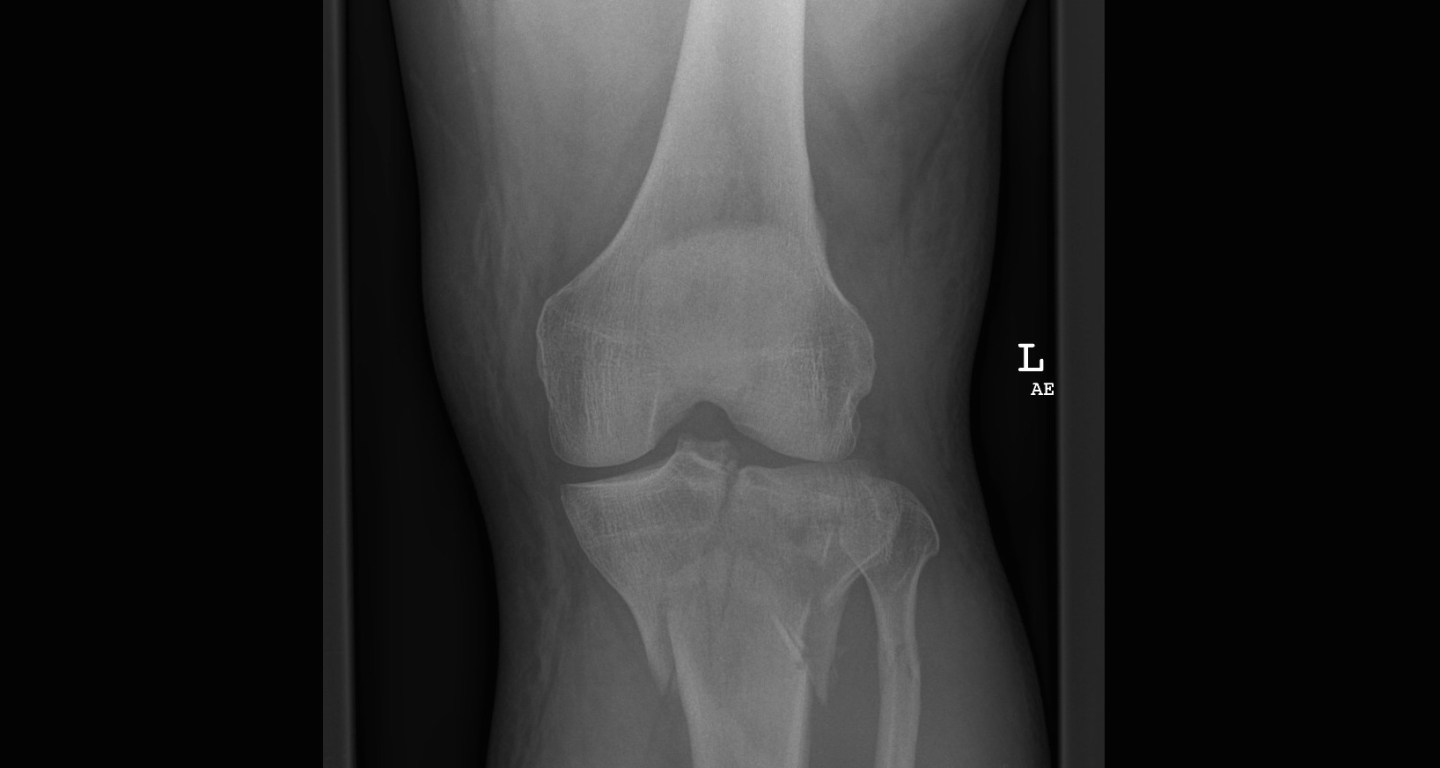

Purpose: The Pittsburgh Knee Rules were developed in order to determine the need for radiographs after acute knee injury secondary to the risk of fracture.